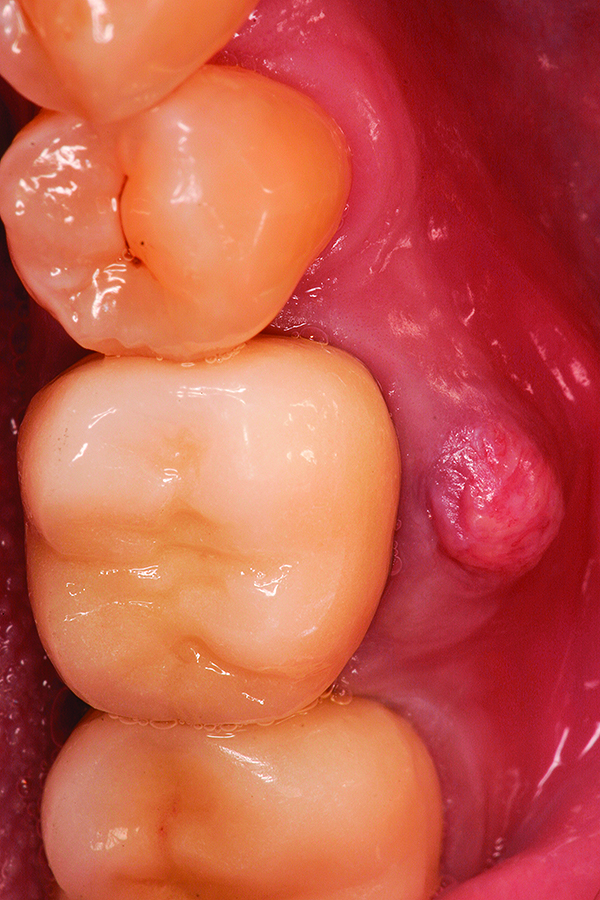

Fig 18. Surgical site at 3 months healing.

Figure 18

Fig 19. Placement of dental implant into healed bone. Note complete circumferential bone surrounding all aspects of the dental implant.

Figure 19